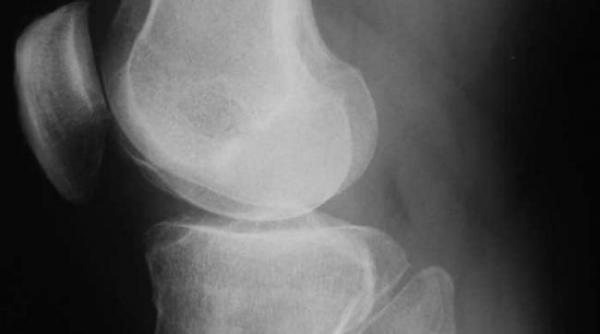

Balamuc în genunchi. Când artrozele au făcut harcea-parcea articulaţia este necesară proteza

Prăpăd în articulaţii

Jurnalul de sănătate: Când scârţâie articulaţiile

Când scârţâie articulaţiile